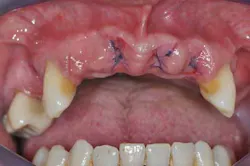

Figs. 3a, b, and c: Extraction of the upper incisors and maxillary removable acrylic placement

- Provisional acrylic removable partial denture placement after the extractions of the upper teeth. It serves as a functional and esthetic test for the rest of the treatment.